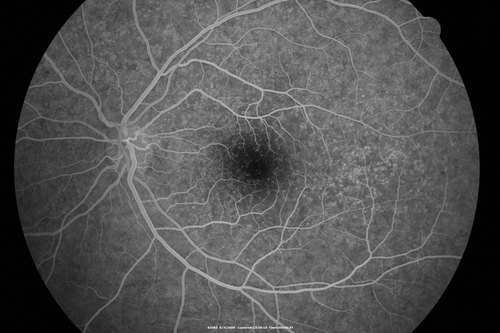

Cuticular Drusen - 26 year old female - Glomerulonephritis

VA 20/25 OU. Images are over 4 years. FA shows starry sky early images - This is because of loss of RPE over the drusen creating very small window defects.